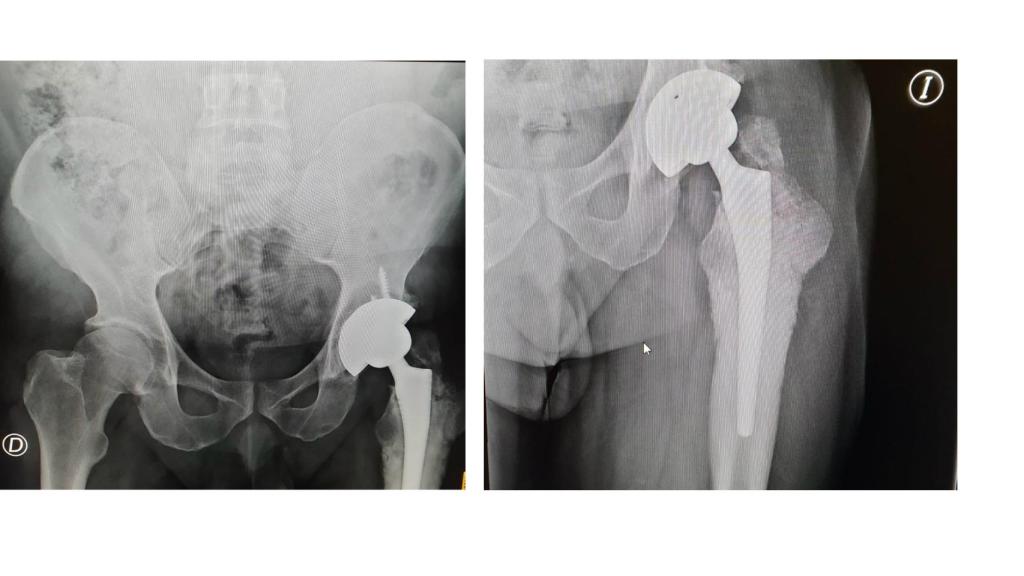

Prótesis de cadera de Pedro Pérez.

Prótesis de cadera de Pedro Pérez. EL ESPAÑOL

Le operaron, retiraron la prótesis defectuosa y cuando la analizaron descubrieron que tenía pequeños tumores alrededor. "Esta operación fue un miércoles, el médico no quedó contento y la repitieron el viernes de la misma semana poniéndome unos anclajes. Comencé una rehabilitación y aún así no podía caminar. A los dos meses me hicieron una tercera operación y otra vez rehabilitación. Desde entonces, vivo con fuertes dolores, tomo hasta 20 pastillas al día. Me han dado de todo: opiáceos, morfina, y ni con esas aguanto el dolor. La morfina no la puedo beber, tampoco me la puedo poner en parches porque me hacen el efecto contrario. Tengo que pincharme en las piernas, en las nalgas...ya no puedo ponerme más pinchazos porque tengo la piel hecha un desastre" cuenta con resignación. "Me han destrozado la vida".

Ahora, tendrá que someterse a una cuarta operación en el Hospital Universitario de Canarias en la que le implantarán una macroprótesis que incluye un fémur artificial. Y el médico no puede asegurarle que quede bien.